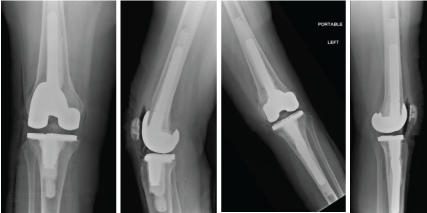

SS is a 60-year-old Female, with no significant past medical history, who presented to our facility with a long-standing history of bilateral knee pain (R > L), however six months prior to presentation she had an acute episode of overnight bilateral knee pain which was so severe that she sought treatment in the emergency room. She denied trauma to either of her knees. She has history of corticosteroid injections into her knee and low back as well a short course of corticosteroid uses for her low back pain. Her physical exam, including her bilateral knee exam was unremarkable. She described the pain as primarily on the anterior aspect of both her knees. Initial radiographs were unremarkable (Figure 14). An MRI was ordered of her bilateral knees which revealed extensive osteonecrosis of bilateral distal femurs and proximal tibias (Figure 15). She received a diagnosis of spontaneous osteonecrosis of the knee and desired staged bilateral Total Knee Replacement (TKR) surgery. She underwent Right TKR initially, followed by Left TKR. Intraoperative photographs can be seen in Figure 16. Postoperatively her pain has markedly improved with unlimited ambulation. Her right knee ROM is 0-135 degrees and her left knee ROM is 0-125 (Figure 17).

One of the remarkable aspects of this case was the diffuse extent of our patient’s osteonecrotic lesion given her relatively benign appearing x-rays. Moreover, the collapse that can be seen of her right femoral trochlear region cannot be appreciated on either the plain radiographic films or the preoperative MRI. One can assume that the severe pain that led to ER eval could have been her lesion collapsing. As one can see we used a stemmed femoral prosthesis to bypass the osteonecrotic lesion on the right knee and stemmed femoral AND tibial prosthesis to bypass the larger osteonecrotic lesion on the left side.

Figure 17: AP and lateral postoperative radiographs. Note that stemmed prosthesis we used in the R femur and Left Femur/Tibia in order to bypass all osteonecrotic lesions. Cement was also used for fixation in both knees. View Figure 17